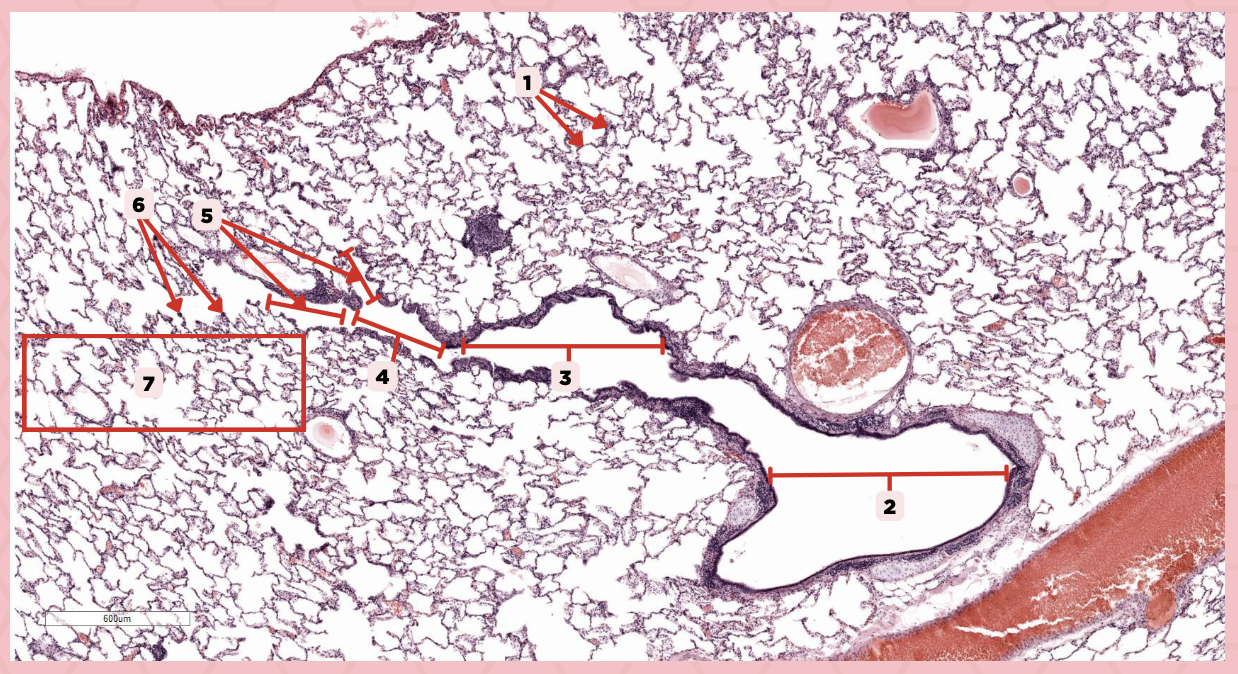

Lumens and Interalveolar septa

Name the irregular spaces and the fine threads of tissue that separate them.

Visceral pleura

Identify the structure labeled as 1.

Alveoli

Identify the structure labeled as 2.

Bigger and smaller intrapulmonary bronchi

What are the two types of intrapulmonary bronchi?

Pseudostratified epithelium (bigger bronchioles), Simple columnar or cuboidal (smaller)

What are the types of epithelium in No. 3?

Interalveolar septa

Identify the structure labeled as 1.

Intrapulmonary bronchi

Identify the structure labeled as 2.

Bronchiole

Identify the structure labeled as 3.

Terminal bronchiole

Identify the structure labeled as 4.

Respiratory bronchiole

Identify the structure labeled as 5.

Alveolar ducts

Identify the structure labeled as 6.

Alveolar sacs

Identify the structure labeled as 7.